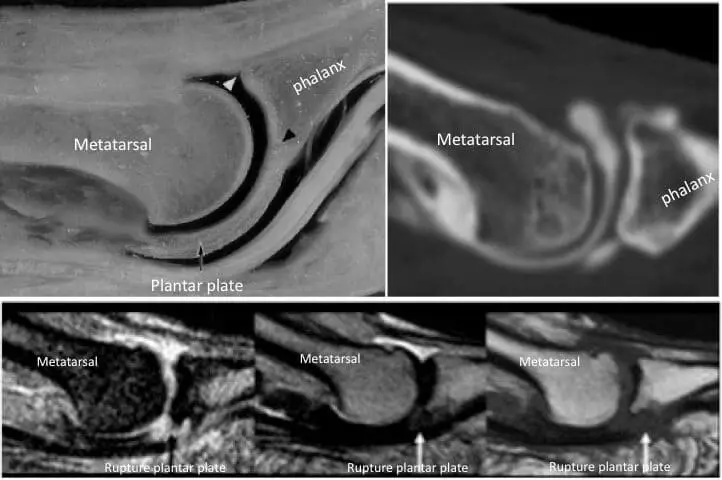

The overpressure may also manifest itself in other ways, but they are always variations on the broad term “metatarsalgia”: a stress fracture of the metatarsal or phalanx, a rupture of the stabilizing plantar structure of the metatarsophalangeal joints:

A dislocation of the toe, the formation of hammer toes,…